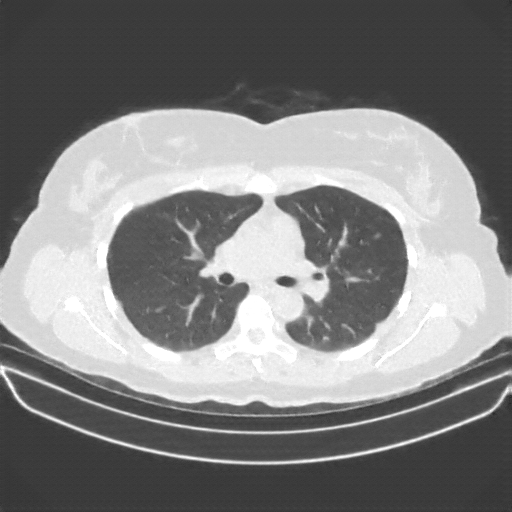

Original VENOUS CT scan

Full window (WL 1023.5, WW 4095 β†’ Low βˆ’1024, High +3071)

Lung window (WL -600, WW 1500 β†’ Low βˆ’1350, High +150)

Mediastinum window (WL 40, WW 400 β†’ Low βˆ’160, High +240)